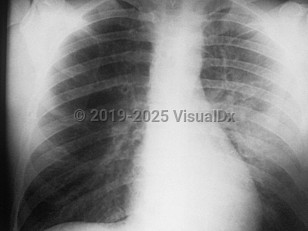

Viral pneumonia